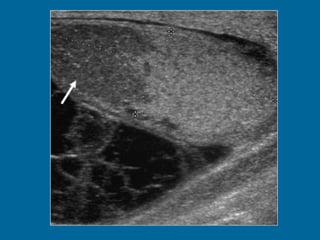

Transverse US scan of the testis shows a normal transmediastinal artery (arrow) as a linear hypoechoic band. Color Doppler flow US (not shown) revealed flow through the vessel.

Transverse US scanof the testis shows a normal transmediastinal artery (arrow) as a linear hypoechoic band. Color Doppler flow US (not shown) revealed flow through the vessel.